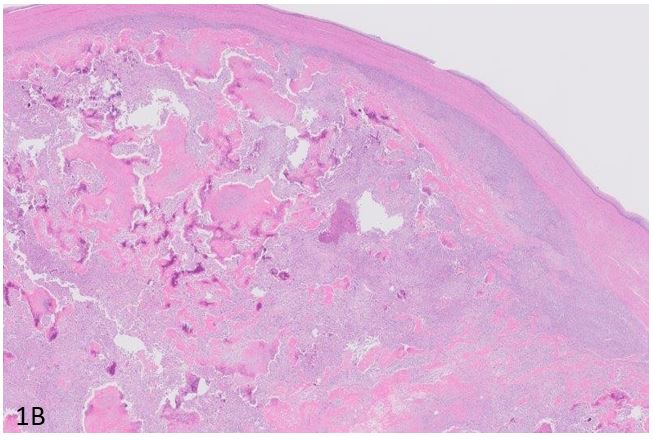

Figure 1B & 1C: Hematoxylin and Eosin-stained section showed spindle cells arranged in fascicles with moderate to severe pleomorphism and multinucleated giant cells with abundant eosinophilic intercellular lace like osteoid with 2-3 mitosis/high power.